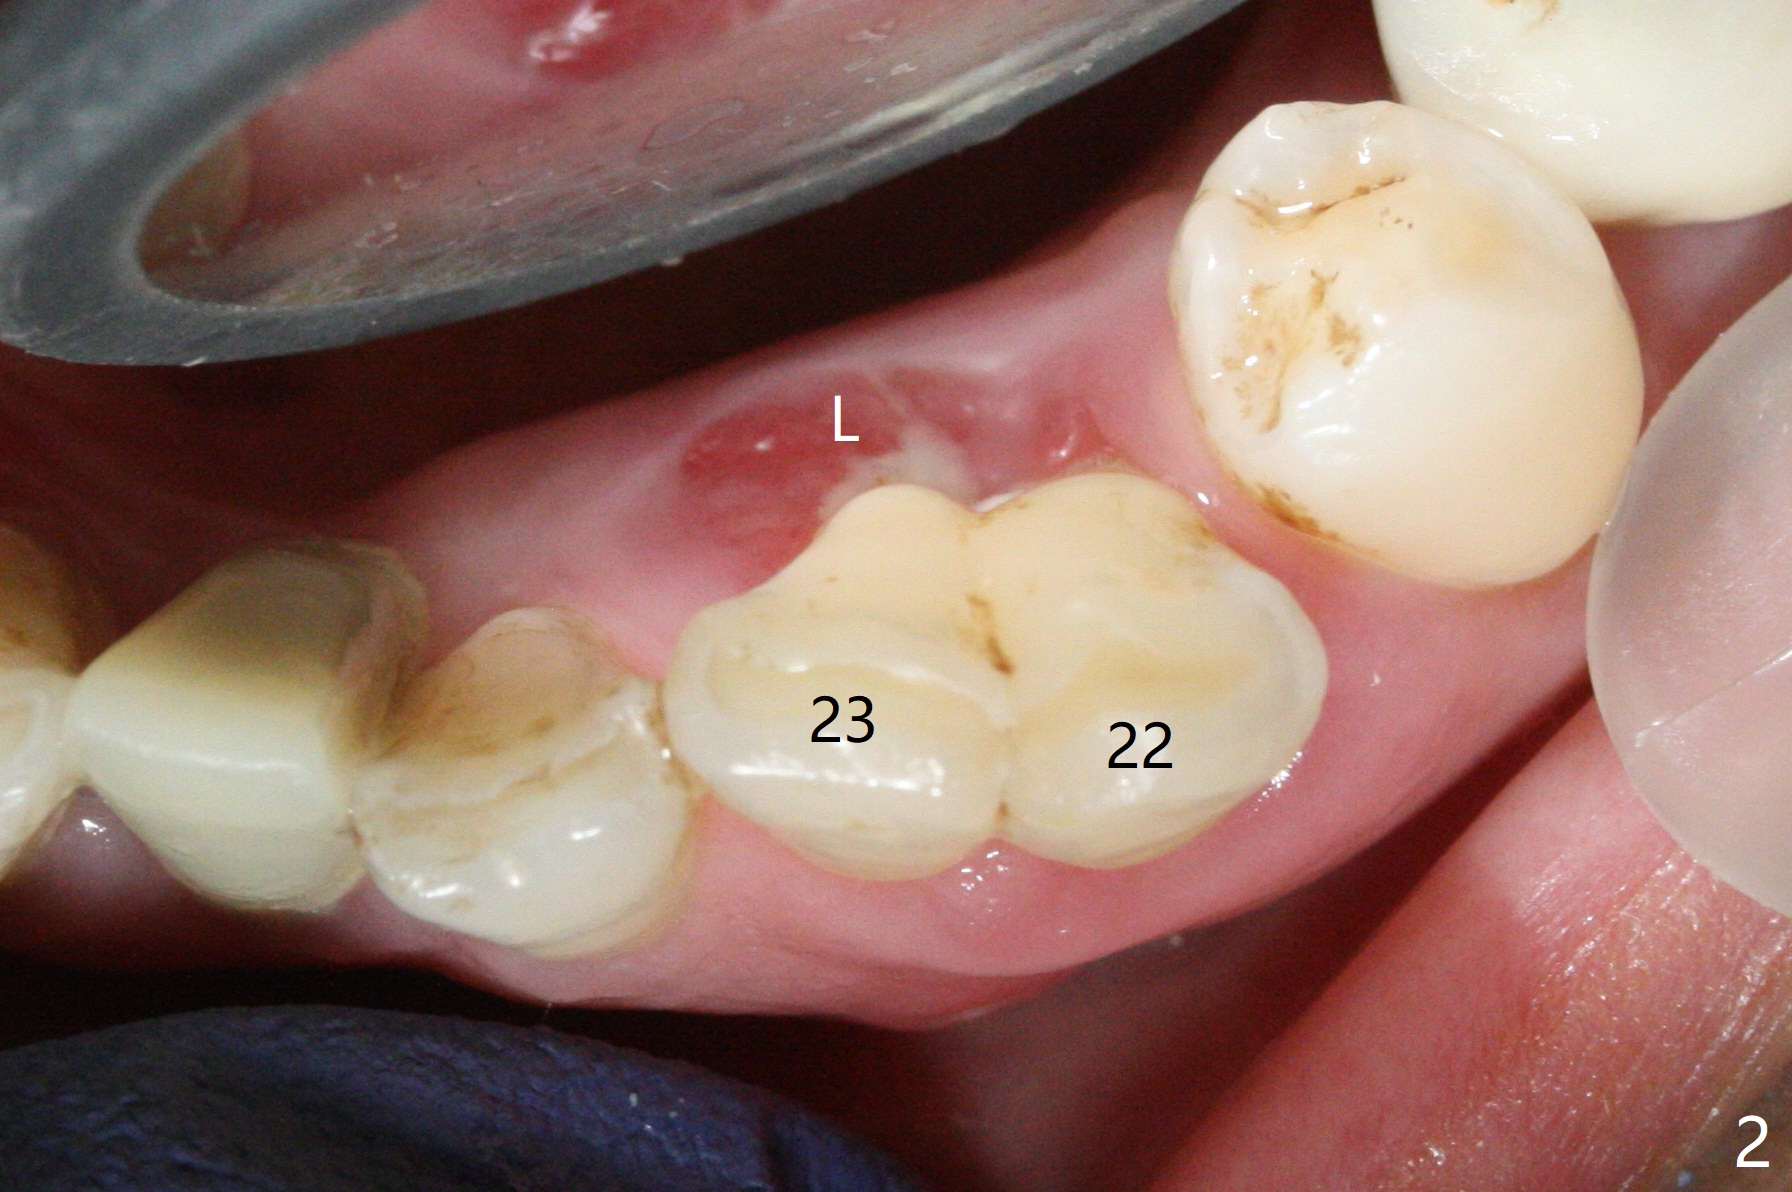

There is a fistula buccal to the apex of the tooth #23 preoperatively (Fig.1), which is related to loss of the buccal plate of the socket of #23. Therefore an implant is placed mainly in the socket of #22 (Fig.3). The lingual (Fig.2 L) gingiva appears to have more extensive inflammation. After extraction, the lingual (Fig.3 L) gingival margin is significantly lower than the buccal one. The lingual crest is ~ 4 mm lower than the buccal one. A 3.8x10 mm dummy implant is placed tentatively with an apical space (Fig.4). When a same dimension definitive implant is placed with 40 Ncm, it is 2 mm below the lingual gingival margin, whereas 6-7 mm below the buccal one (Fig.5). Vanilla graft is placed before placement of a 5.5x4(5) mm abutment (Fig.6,7). There is a 2-3 mm lingual (L) gap to be filled with the allograft secondarily to prevent periimplantitis (Fig.7). Later the abutment is changed to a longer and smaller one (Fig.8) with more of the allograft (*). After trimming of the abutment (Fig.9 (*: papilla between the fused teeth)), an immediate provisional is fabricated to close the socket (Fig.10, similar to Fig.1). The majority of the bone graft seems to be in place 8 months postop (Fig.12). The implant appears to have been placed buccal, consistent with the thin and slightly erythematous buccal gingiva (Fig.13). The ridge completely regenerates 2 years post cementation (Fig.14).